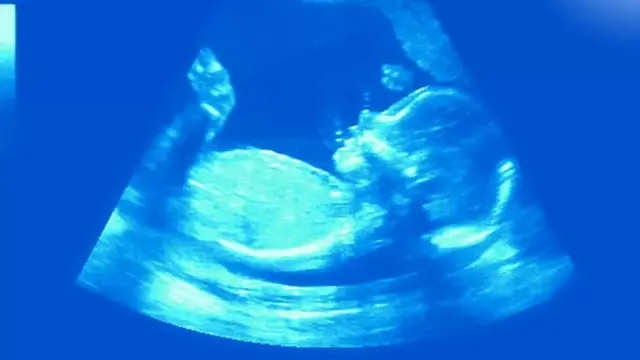

حاملہ ماؤں کے رحم میں قبل از پیدائش الٹراساؤنڈ چیک کے دوران صحت مند جنینوں میں بھی ہچکی دیکھی گئی ہے۔ درحقیقت کچھ محققین کا خیال ہے کہ پیدائش کے فوراً بعد بچے میں پھیپھڑوں کو سانس لینے کے لیے تیار کرنے کا عمل ہچکی کی وجہ سے شروع ہوتا ہے۔